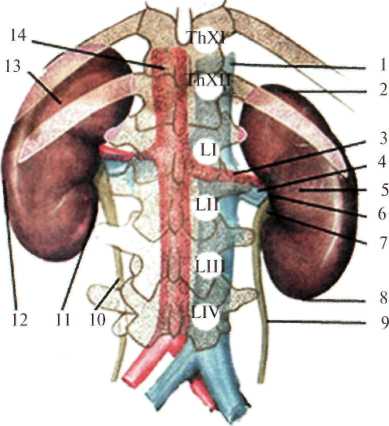

Скелетотопически почки располагаются на уровне XI-XII грудных и II-III поясничных позвонков, правая почка расположена выше левой. Различают высокое и низкое положение почек (рис.2.5). При высоком положении верхний полюс почки расположен на уровне XI, при низком – на уровне XII ребра.

Рис. 2.5 Скелетотопия почки сзади.

1 – v. cava inferior; 2 – extremitas superior; 3 – a. renalis dextra; 4 – v. renalis dextra; 5 – ren dexter;

6 – hylum renale; 7 – pelvis renalis; 8 – extremitas inferior; 9 – ureter dexter; 10 – ureter sinister; 11 – margo medialis; 12 – margo lateralis; 13 – ren sinister; 14 – aorta abdominalis.